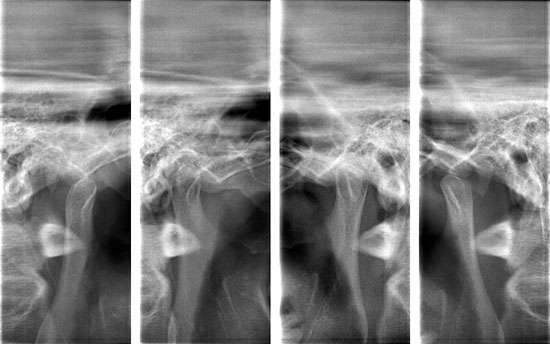

術前後のレントゲン写真

このように横に生えていると、7番目の歯と親知らずの隙間に細菌が溜まり、虫歯になったり、周囲の歯肉が腫れたりする原因となります。

術 前

術 後